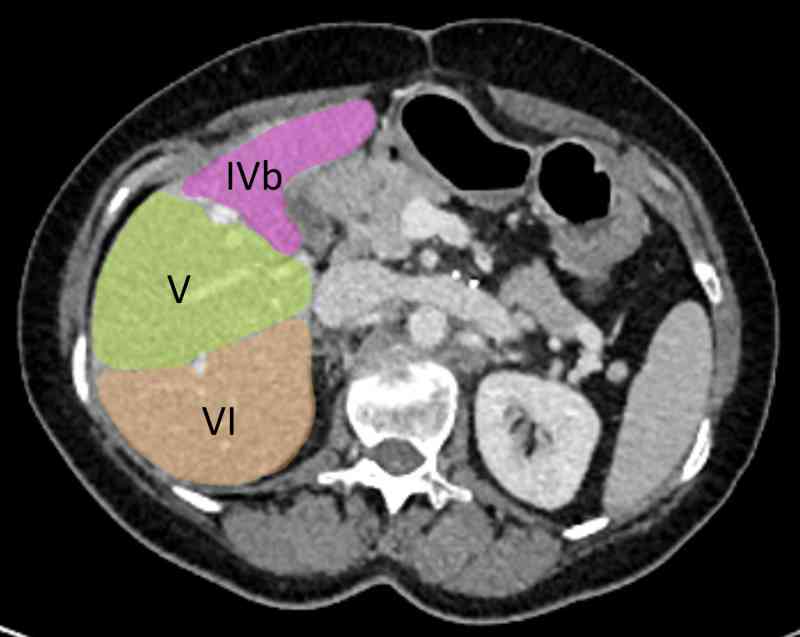

Liver segments are the caudate lobe (segment I) and each region of the liver when it is divided by the portal and hepatic veins. Segments below the portal vein from left to right are III, IVb (remember it is inferior using b for base), V and VI. Segments above the portal vein are II, IVa VIII and VII. When working in this order is is not immediately apparent the order that the segments take e.g. VII seems to be after VIII. Instead count starting with the caudate lobe, move across to segment II (superior, most leftward), move down to III, across right to IV, V, and VI, then straight up to VII and across left to VIII. Trace this out in your mind and on screen and it makes sense.

If you want to count in order, count I and II above, move to the image below and count III, IV, V, and VI, skip the third image and count VII and VIII on the fourth. Observe the order you moved around the liver when counting in this manner.